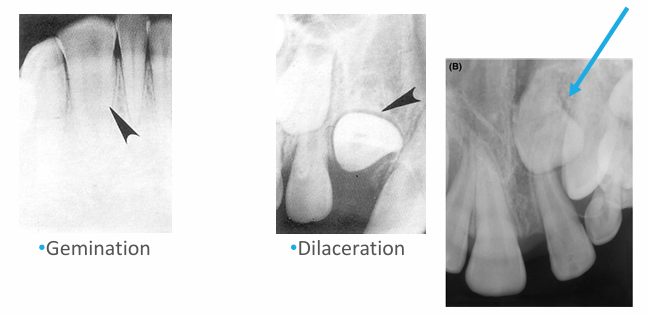

panoramic radiograph

-evaluate growth and development

-take pans in children if unerupted teeth exist that should be erupted

-some practitioners say every 3 yrs starting at age 6

-look at overall development of child

-23, 24, 25, 26, 1st year molars present = good time to take pan

-anomaly: ankylosis

-peg lateral

-supernumerary primary lateral

-count the teeth

-fusion

-supernumerary tooth

-missing lateral

-concrescence: cementum fuses together

-unfavorable resorption pattern of roots

-retained primary root tips

-common in kids with high caries → don’t get tx and teeth just crumble